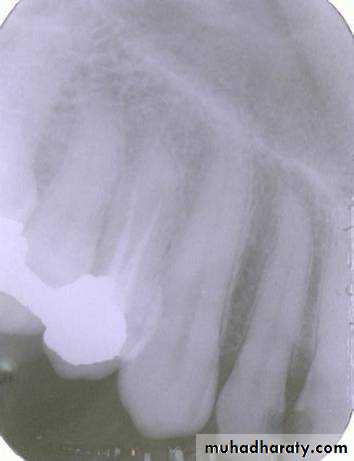

premolar filmThe arrow in the canine film is pointing to the gutta percha in which canal of the maxillary first premolar?

2

The arrow identifies the lingual canal. The tube head moves mesially from the premolar film to the canine film (beam directed more distally) and the gutta percha indicated by the arrow also moves mesially. (See following slide).

PID

lingual

buccalWhen the tube head is moved mesially, with the beam directed distally, the two canals, which are initially superimposed (premolar periapical above) will separate. The lingual canal (red arrow) will follow the tube head movement and the buccal canal (blue arrow) will move in the opposite direction, as seen on the canine film.